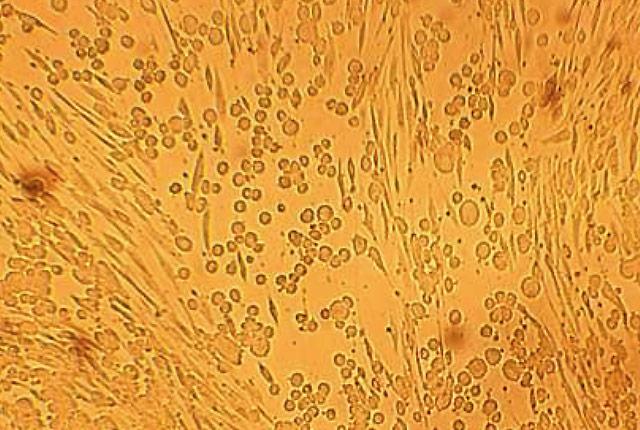

Researchers found that HSV-1 and HSV-2 are mixing together to result in several new, different recombinant versions of herpes.

Both viruses look alike clinically and are sensitive to the same drug, acyclovir. But they are genetically different. HSV-1 most commonly affects the mouth, while HSV-2 usually causes genital lesions.